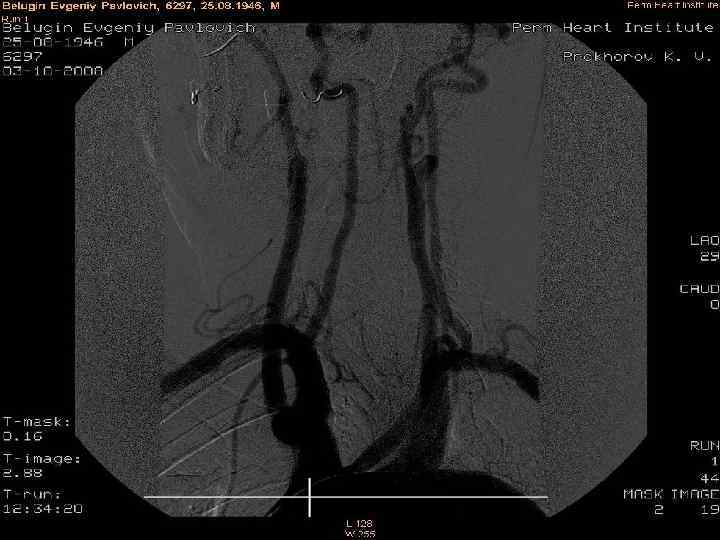

Коронография Коронарграфия- тамырға контраст жібере отырып, рентген сәулесінің көмегімен коронар артериясын диагностикалау әдісі. Бұл жүрек инфарктін алған науқастар үшін немесе жүректің ишемиялық ауруын дәлелдеп не жоққа шығаруда алтын стандарт.

Коронография - жүректiң қан тамырларын қарама-қарсы зерттеу әдісі. Бұл зерттеулер диагноздың қойылуы, диагноздың түзетуi, емделушiнiң емдеуiн тактиканың анықтауы үшiн диагностикалық мақсатпен жүргiзiледi.

Коронография

Коронография арқылы зеттеу жергілікті анестезиямен жүргізіледі. Сол жақ шап аймағына жергілікті жансыздандырудан кейін ине кіргізіледі. Дәрігер құрамында йоды бар контрасты зат енгізеді. Контрасты зат тамырларға тарап коронарлық артерияларға жетіп жүрек бұлшық еттерін жабдықтайды. Экранда керекті қан тамырларының суреті пайда болады. Қалыпты жағдайда адамда екі коронарлық артерия яғни оң және сол жақ болып бөлінеді.